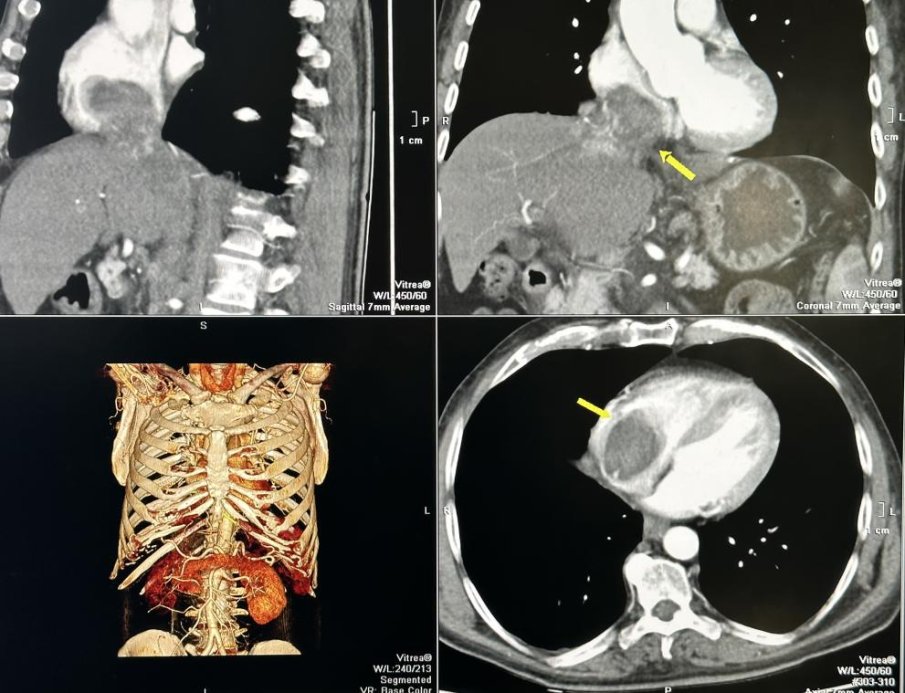

Туморът с размери 7 на 9 см. е ангажирал и изпълнил почти изцяло кухината на дясното предсърдие на сърцето и е застрашавал да запуши белодробните артерии и белия дроб.

От болницата уточняват, че след постъпването на пациента е направен скенер, от който се установяват злокачествените образувания в кухините на сърцето и наличието на две огромни туморни огнища в черния дроб.

Екип на Клиниката по кардиохирургия под ръководството на проф. Димитър Петков премахва напълно туморите от сърцето и от цялата долна празна вена, намираща се в чернодробния участък.